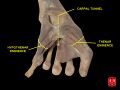

Wrist joint. Deep dissection.Anterior, palmar, view.

-

Carpal tunnel and thenar and hypothenar eminences